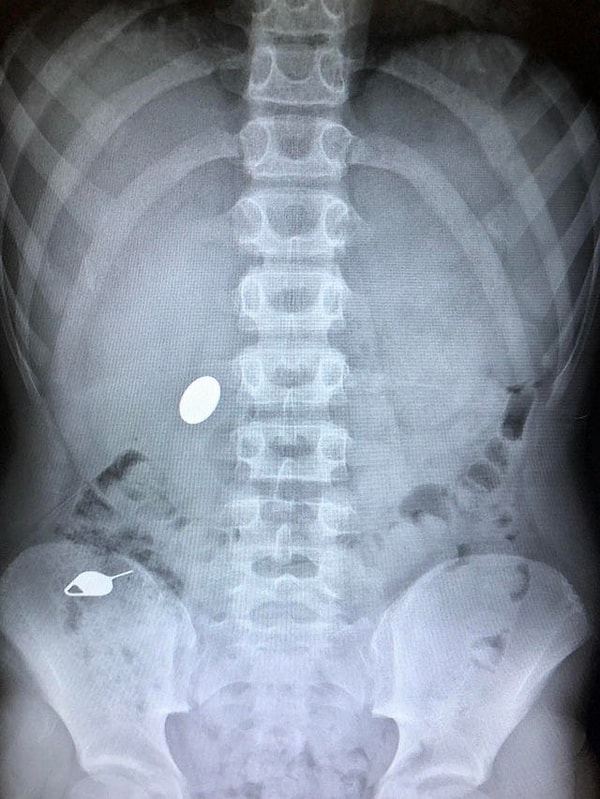

1. «Сын проглотил монетку, пока показывал брату, как он за день до этого проглотил ключ»